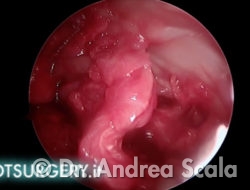

La telecamera è stata introdotta all’interno della regione calcaneale. Dal lato opposto penetra la sonda che consente di esaminare le strutture da curare. Nel caso particolare si vedono i residui della voluminosa borsite retrocalcaneale che deve essere asportata. La parte malata viene rimossa mediante strumenti motorizzati ed eliminata mediante l’aspiratore.